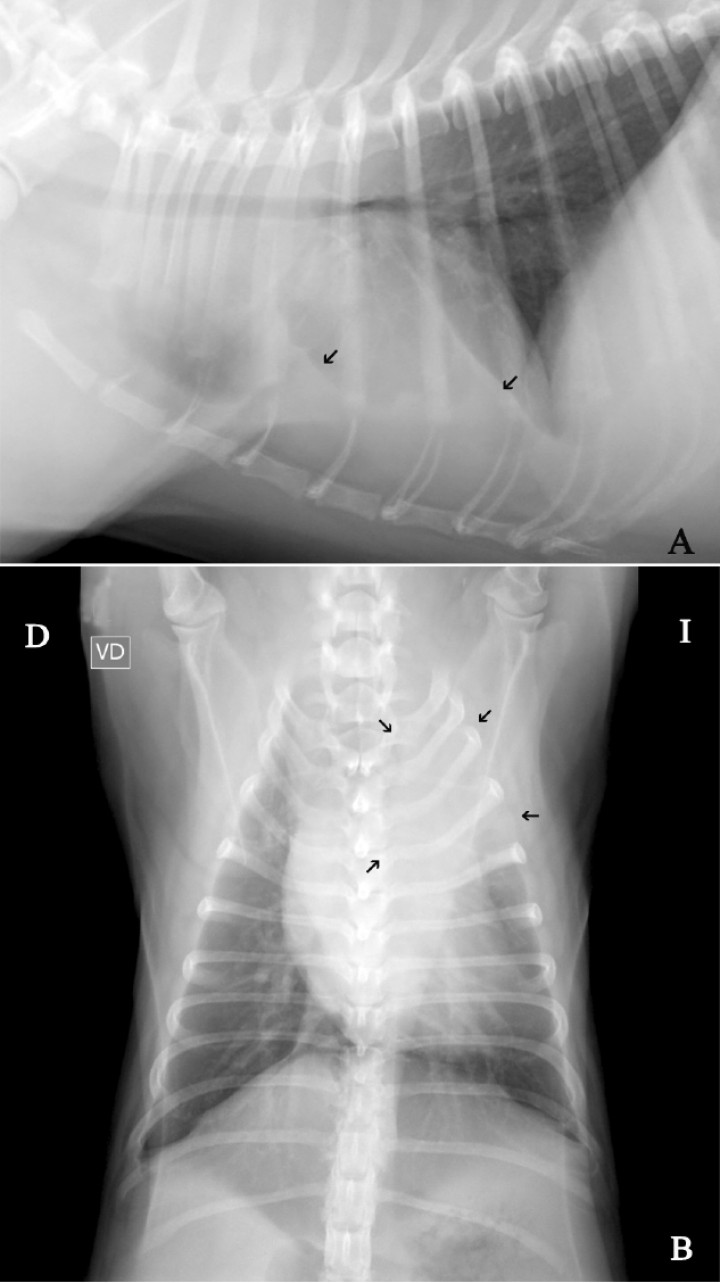

Se presenta en el Hospital Clínico Veterinario un perro de raza carlino, de 11 meses de edad, entero y 9,6 kg de peso, por un cuadro clínico desde hacía dos semanas con crisis de tos y disminución del apetito. El veterinario remitente le había pautado un tratamiento médico a base de codeína, doxiciclina y furosemida, respondiendo con una leve mejoría clínica. En el examen físico se evidenció, como único dato reseñable durante la auscultación torácica, un aumento de los sonidos traqueales y un sonido de roncus. El análisis sanguíneo reveló leucocitosis con desviación a la izquierda. Se realizaron radiografías de la cavidad torácica (Fig. 1).

<p>Tórax en un perro carlino de 11 meses e historia de tos y disminución del apetito. (<strong>A</strong>) Proyección lateral derecha. (<strong>B</strong>) Proyección ventrodorsal.</p>

Tórax en un perro carlino de 11 meses e historia de tos y disminución del apetito. (A) Proyección lateral derecha. (B) Proyección ventrodorsal.

El diagnóstico diferencial de un paciente con un cuadro de tos crónica y hallazgos radiográficos observados en el parénquima pulmonar (Fig. 2) como son aumento de la opacidad en la parte craneal del lóbulo craneal izquierdo y leve efusión pleural es el de patología del lóbulo craneal izquierdo. Dentro de las alteraciones compatibles se debería incluir, en orden de mayor a menor probabilidad: la torsión del lóbulo pulmonar, consolidación pulmonar, neumonía y neoplasia.

<p>(<strong>A</strong>) Proyección lateral derecha de tórax. Se aprecia la presencia de efusión pleural (flechas negras). (<strong>B</strong>) Proyección ventrodorsal. Se visualiza un incremento de la opacidad en la zona del lóbulo craneal izquierdo (flechas negras).</p>

(A) Proyección lateral derecha de tórax. Se aprecia la presencia de efusión pleural (flechas negras). (B) Proyección ventrodorsal. Se visualiza un incremento de la opacidad en la zona del lóbulo craneal izquierdo (flechas negras).

Los hallazgos radiográficos que se han descrito en la torsión pulmonar incluyen derrame pleural, atelectasia lobar, consolidación lobar, desplazamiento mediastínico, pneumotórax y pneumomediastino. Estos signos se consideran inespecíficos, ya que también pueden observarse en diferentes procesos, como la neoplasia y la hernia diafragmática. En casos de efusión pleural, este líquido suele ser serosanguinolento o quiloso, con alto número de eritrocitos y leucocitos. Las anomalías radiográficas más características de esta patología son la presencia de un patrón de gas vesicular y un bronquio estrecho,[ Gicking JC, Aumann M. Lung lobe torsion. Compend Contin Educ Vet, 2011; 33: E1-E4. [PubMed] , Agut A, Carrillo JD, Seva J, Soler M, Laredo FG. What is your diagnosis? Lung lobe torsion. J Am Med Assoc 2013; 243: 333-335. [PubMed] ] aunque no se llegan a visualizar en todos los casos. En nuestro paciente únicamente se evidenciaba un aumento de la opacidad en la zona del lóbulo craneal izquierdo y leve efusión pleural, requiriéndose de pruebas de imagen más avanzadas como la tomografía computarizada (TC) para llegar al diagnóstico definitivo.